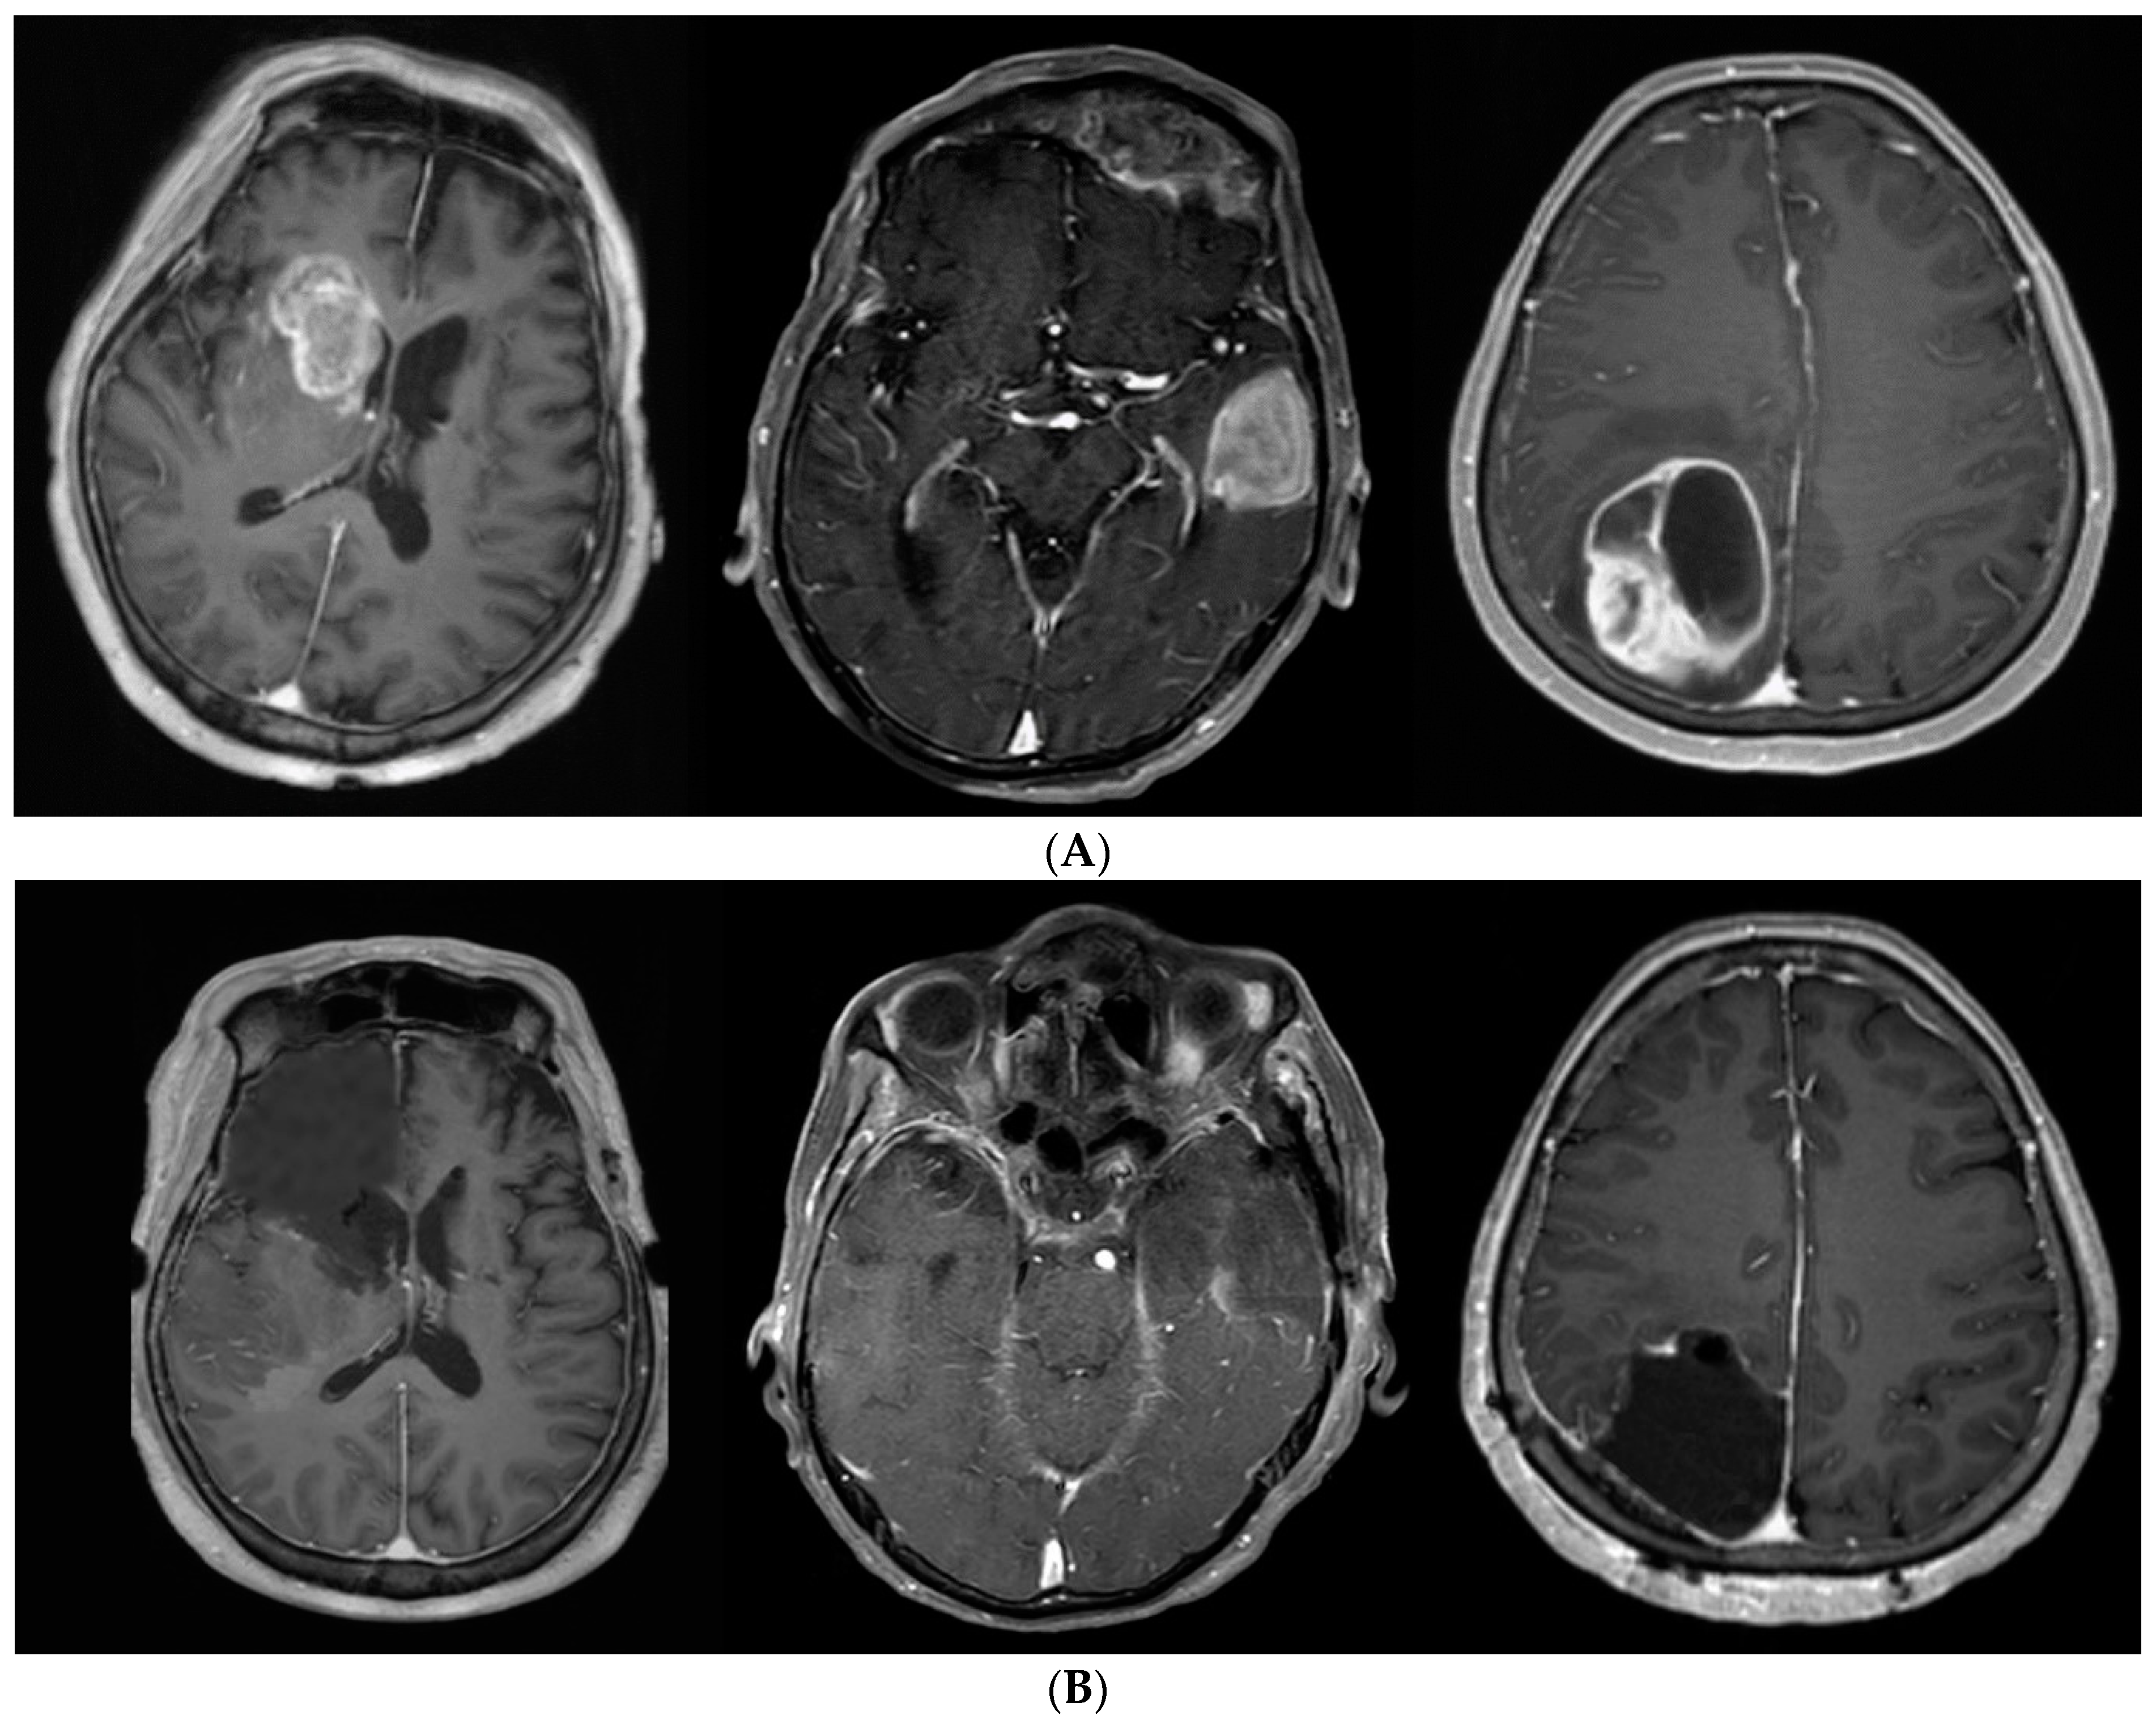

After tumor removal, the anterior pole of the frontal lobe was removed under navigation guidance. Next, a subpial dissection was performed at the medial, lateral, and inferior surfaces of the frontal lobe, while preserving the surrounding vascular structures and olfactory nerve. The posterior margin of the frontal lobectomy was just beneath the coronal suture, which is approximately 1–2 cm anterior to the precentral sulcus. An awake craniotomy was performed in cases when the tumor was near an eloquent area. Moreover, tumor removal and/or additional anterior-temporal lobectomies were performed for cases with temporal-lobe tumors. The posterior resection margin was approximately 5–6 cm in the case of the non-dominant hemisphere and 3.5–4.5 cm in the case of the dominant hemisphere from the temporal pole. When the tumor was located in the occipital lobe, the whole occipital lobe was resected regardless of visual symptoms. Figure 2 illustrates some representative cases. We performed frontal, temporal and occipital lobectomy.

Figure 2. (A). Preoperative axial T1-weighted gadolinium-enhanced MRI showing a GBM involving the frontal, temporal and occipital lobes. (B). An example of a patient in whom SupTR was achieved. After complete resection of the tumor, a frontal, temporal and occipital lobectomy was performed.